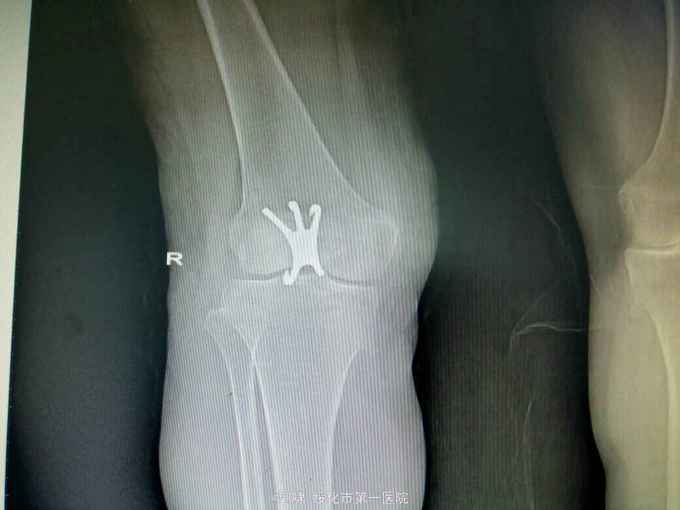

左膝关节摔伤,肿胀,畸形,活动受限一小时。收入院。患者于一小时前滑倒摔伤。当即倒地,左膝关节肿胀,畸形不能行走。门诊拍片示:左膝关节髌骨骨折,断端移位。门诊以左髌骨骨折收入院。

左膝关节肿胀,局部畸形,不能下地行走。浮髌试验阳性。拍片示:左髌骨骨折。

诊断:左髌骨骨折。立即予以腰麻下行切开复位内固定术。术中复位骨折,缝合筋膜,冰水浸泡髌骨爪约10分钟。待髌骨爪变软。选取合适大小的髌骨爪。应用记忆合金髌骨爪内固定。立即用40°温盐水热敷局部。使记忆合金加速抓紧。环抱。缝合爪齿二道,防止脱落。缝合关节囊,韧带组织。术毕。

应用记忆合金髌骨爪内固定髌骨骨折。手术时间基本在20----30分钟内都可以完成。局部损伤小。固定牢靠,确实。患者二个月就可以下地负重活动。具体手术技巧。一是髌骨爪提前用冰盐水侵泡10分钟左右。待记忆合金变软即可使用。二。固定牢靠后立即用40°温盐水热敷。使其快速抓紧。三,缝合爪齿,防脱。四如有粉碎,小的骨块可以缝合筋膜固定。有大骨块,最好环扎钢丝,或穿针固定,有时穿骨隧道钢丝捆扎。效果也不错。只要做到以上几点。安全无忧了!以下是以前做的片子。可以看一看。